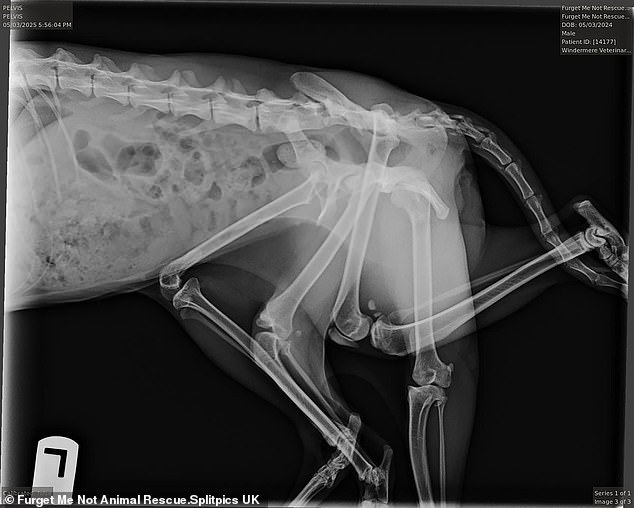

In Canada, a cat was born with six legs.

Veterinarians believe Bitsy's extra limbs are the remains of a twin she devoured in the womb.

Unfortunately, three of the cat's six paws were non-functional and prevented her from moving.

To help the animal, doctors removed three paws and part of her pelvis.